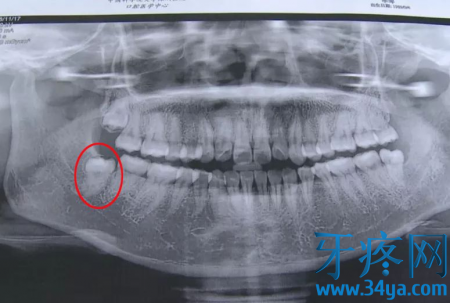

记者通过采访医生得知,她长的这颗智齿比一般的智齿拔起来困难得多,因为她的这颗智牙需要做很多项检查和护理,也多了很多步骤,所以这个收费也是按照标准收取的。

▲阻生智齿